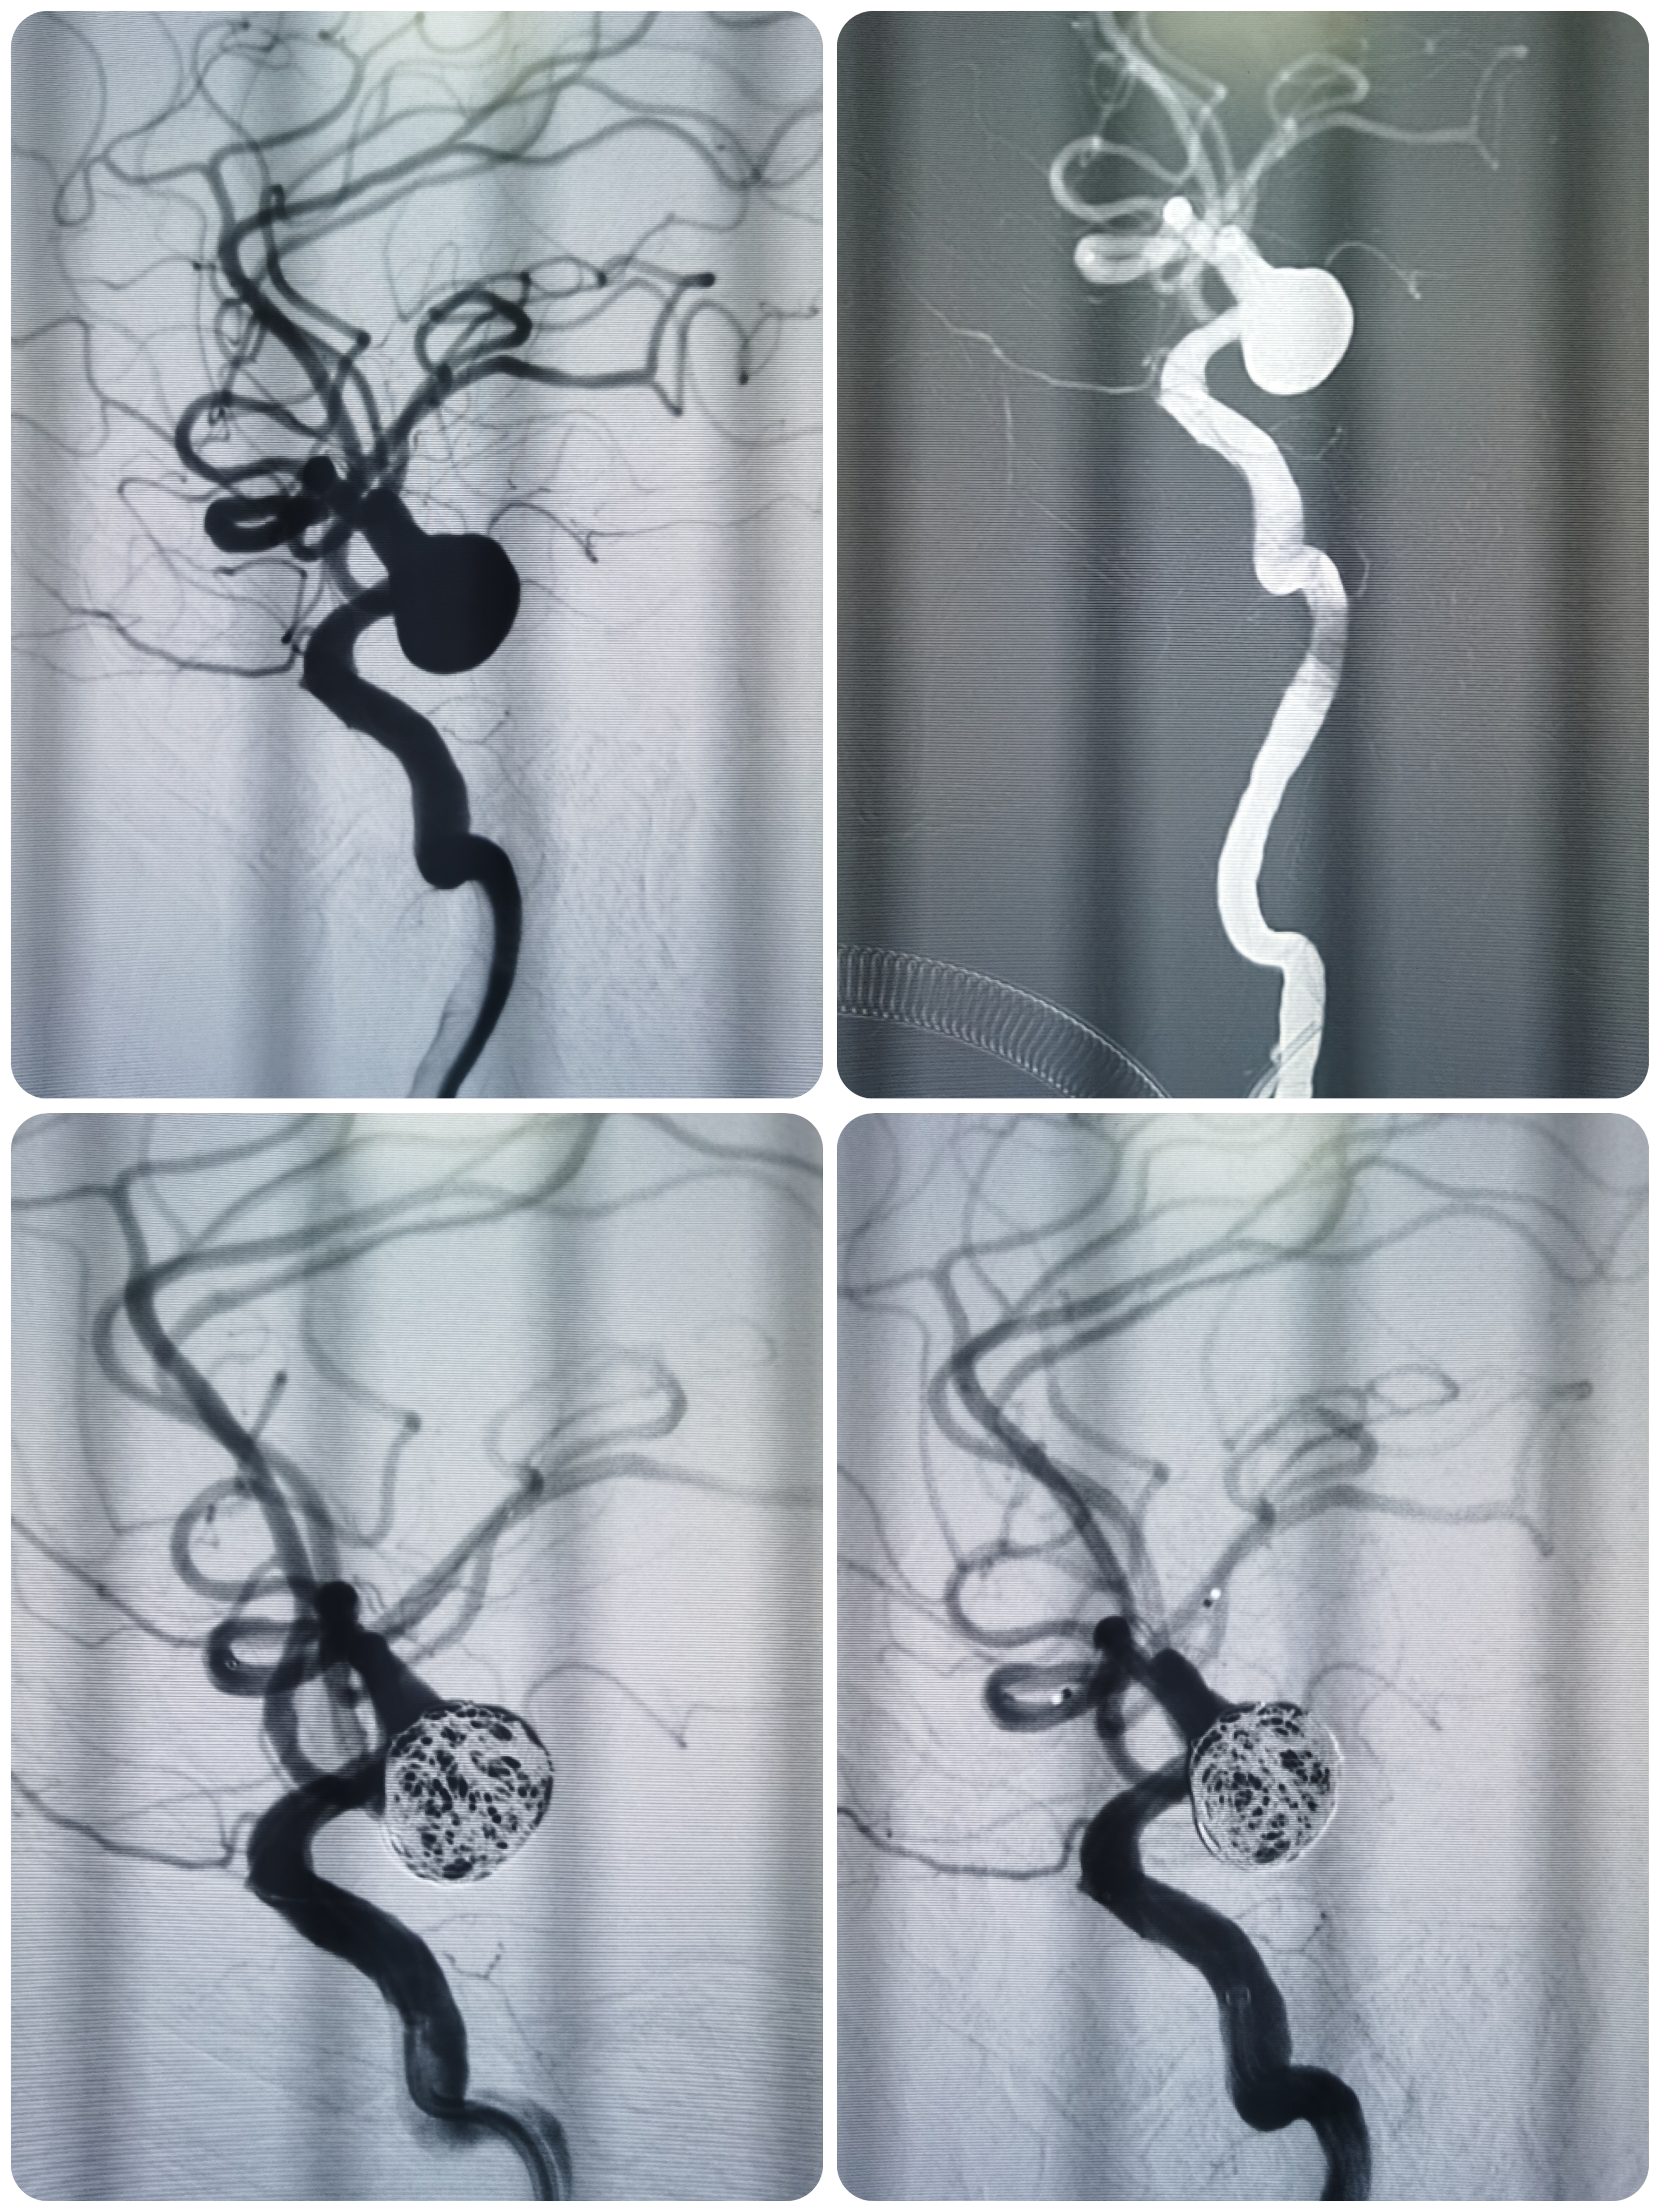

路途下中间导管到位至于左侧颈内动脉海绵窦段,微导丝携SL10微导管于瘤内成攀技术顺利到达左侧大脑中动脉远端。

微导管塑形后送入动脉瘤腔内,首枚填入12*30成蓝圈,再依次填入10*30,9*30,8*30弹簧圈,造影见瘤体上部致密填塞,载瘤动脉通畅。

利用微导丝将栓塞微导管再重新选入动脉瘤体下部,依次填入7*30,7*20弹簧圈,复查造影见动脉瘤大部填塞,瘤内造影剂滞留明显载瘤动脉通畅。

术后即刻造影见动脉瘤栓塞较完全。

术后造影见动脉瘤栓塞较为完全,载瘤动脉通畅,遂未再植入支架,逐渐撤出各级导管,缝合股动脉结束手术。